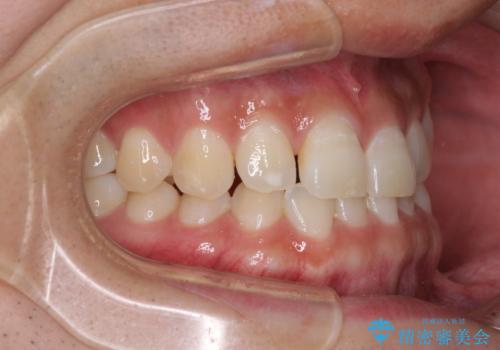

- 上顎前歯の隙間を気にして来院された患者様です。

下顎前歯に叢生がありましたが、特に気にしていらっしゃいませんでした。

下顎臼歯にインプラント補綴治療がされており、全顎治療するにはクラウンの作り替えが必要となる旨を説明し、ワイヤー装置により上顎のみの矯正治療を行うこととしました。

下顎前歯の叢生解消も提案しましたが、上顎の隙間が閉じたことで満足されました。